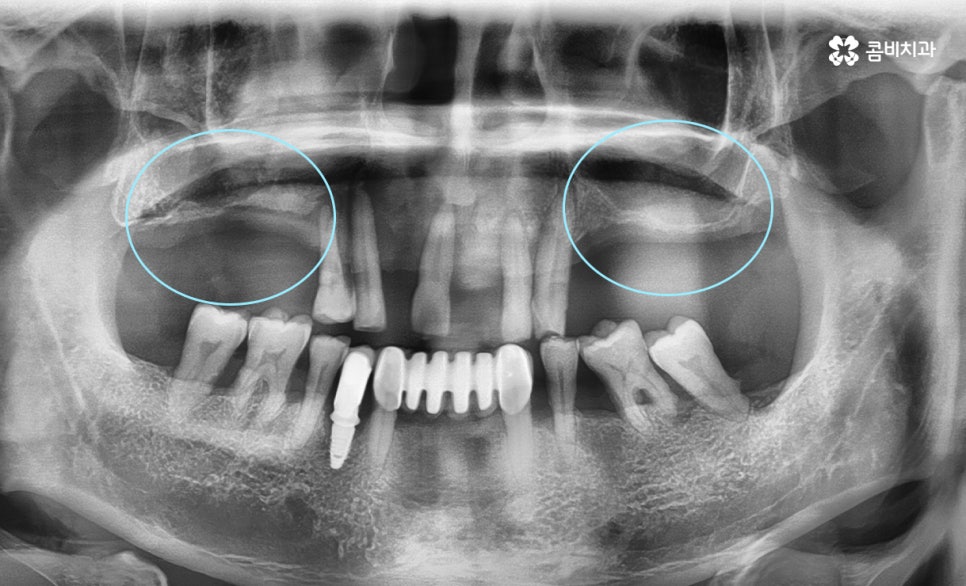

전악 임플란트 케이스로 당뇨 및 합병증으로 인해 잇몸뼈가 녹아서 잇몸이 주저앉은 상태

상악동 거상술이 필요한 임플란트 수술 케이스

위 이미지 사례에서 보실 수 있듯이

임플란트를 식립할 잇몸뼈가 부족한 경우입니다.

잇몸이 내려앉은 상태에서 공기주머니까지 주저앉은 상태

상악동 거상술이란?

전악, 즉 윗니를 상실한 경우에 치아가 빠진 채로 시간이 흐르거나

치주염으로 잇몸뼈가 파괴된 경우 잇몸이 주저앉으면서

상악동이 점점 커지고 밑으로 내려오는 경우가 있습니다.

이때 임플란트를 식립할 공간이 부족해지게 되는데

상악동과 위턱뼈 사이에 있는 상악동 막을

다시 위로 들어올리고 뼈이식을 하는 것이 상악동 거상술 입니다.